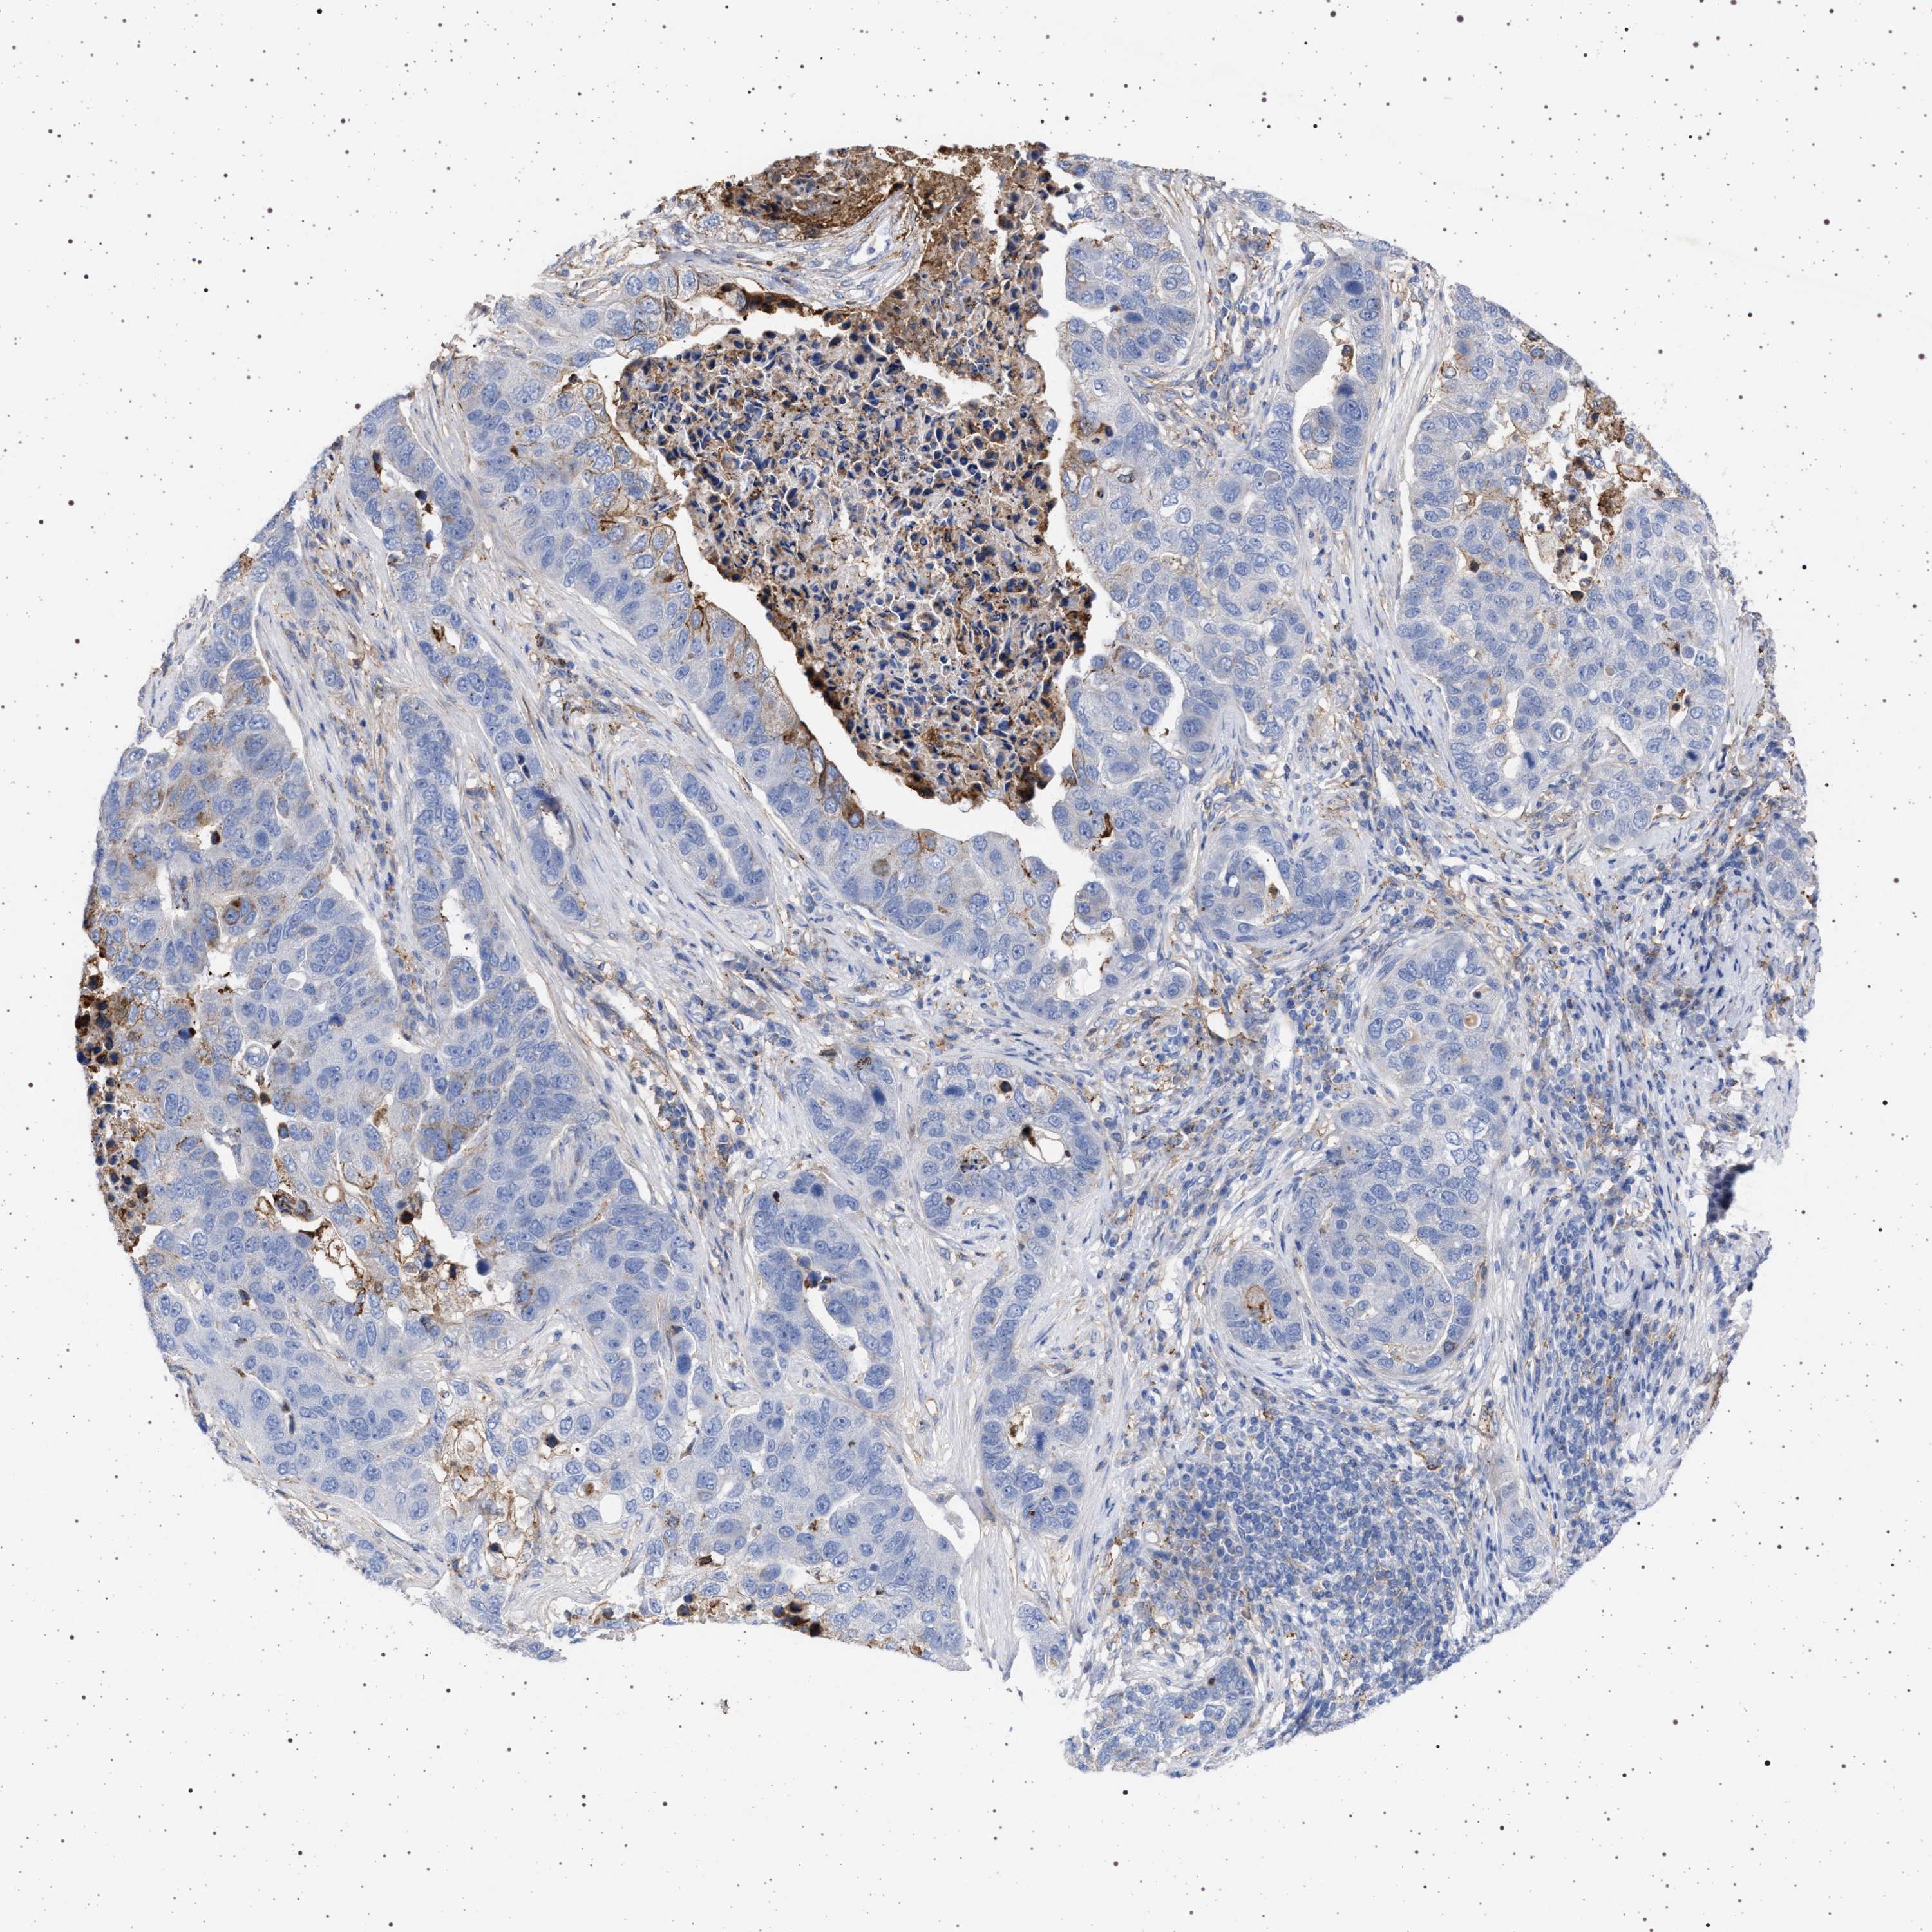

PANCREATIC CANCER - Protein expressioni

A mouse-over function shows sample information and annotation data. Click on an image to view it in a full screen mode. Samples can be filtered based on level of antibody staining by selecting one or several of the following categories: high, medium, low and not detected. The assay and annotation is described here.

Note that samples used for immunohistochemistry by the Human Protein Atlas do not correspond to samples in the TCGA dataset.

Antibody stainingi

Antibody staining in the annotated cell types in the current human tissue is reported as not detected, low, medium, or high, based on conventional immunohistochemistry profiling in selected tissues. This score is based on the combination of the staining intensity and fraction of stained cells.

Each image is clickable and will lead to virtual microscopy that enables deeper exploration of all samples and also displays staining intensity scores, fraction scores and subcellular localization as well as patient and tissue information for each sample.

Antibody HPA021602

Antibody HPA048823

Antibody CAB000668

Antibody CAB016678

Adenocarcinoma, NOS